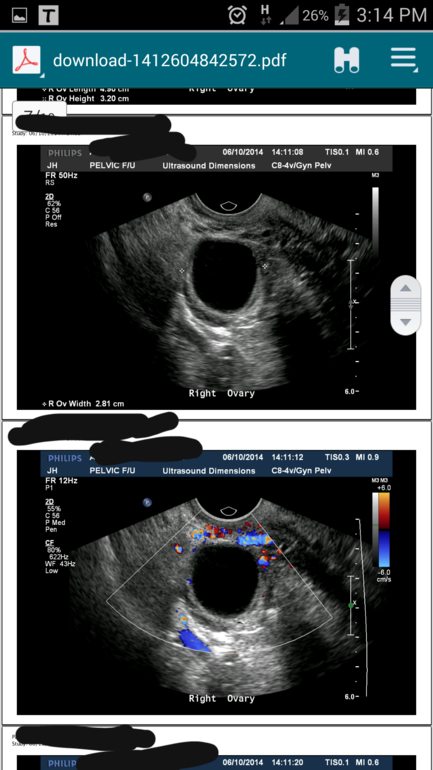

Вот еще фото...

Яичник в другом ракурсе

Аминь!Какие у вас фотки с узи! И доплер (кровоснабжение в цвете) и яичник в двух ракурсах!!! я в шоке!!!!!! аааа Дублин.......ура ирландским узистам!!!!!!!!!!!!!

Ну вот так вот))) просто оборудование хорошее, и на вид очень современное! Да правда два раза такая не очень узистка попалась....кстати, все фото снимки они делают для себя.Я просто прошу выслать их на майл.А обычно они дают один листочек и там 3 строчки написано)))